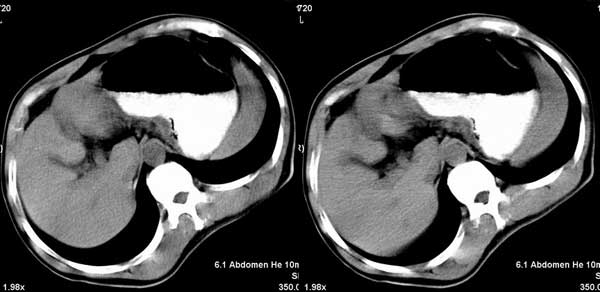

以下是引用听蝉观竹在2005-2-15 23:30:28的发言:[br]胃窦癌。[br]建议做胃镜检查并活检。